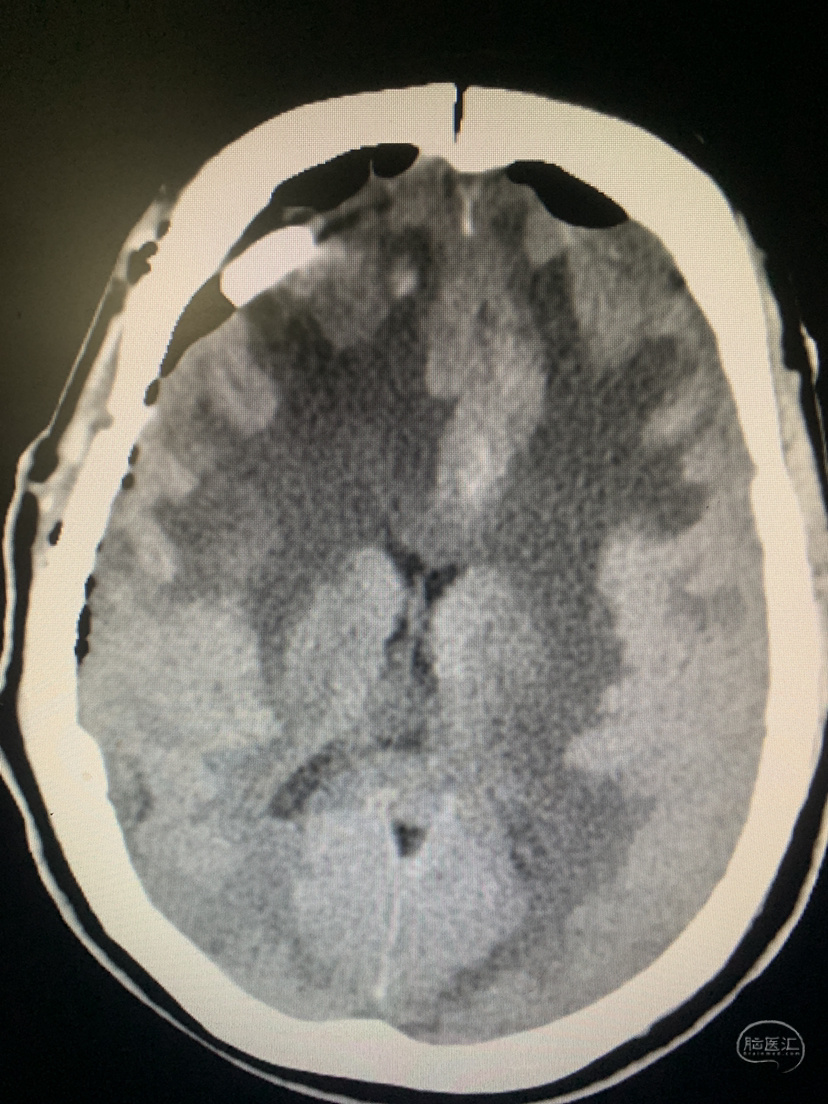

术前CT

术前CT